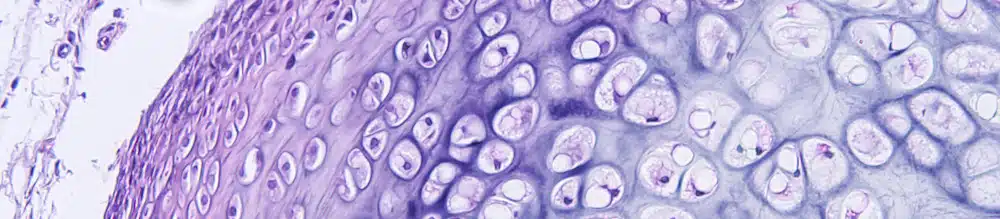

Zunächst experimentierten die Forscher mit Knorpelgewebe im Labor. Sie bauten in ihrer Versuchsanordnung ein konstantes schwaches elektrisches Feld über einer Zellkultur auf. Dieser Forschungsansatz brachte ein bemerkenswertes Ergebnis: Die elektrischen Ströme stimulierten die Zellkultur so stark, dass sie neues Knorpelgewebe ausbildete.

In einem nächsten Schritt ging es darum, herauszufinden, ob die Entdeckung, dass Knorpelgewebe im Labor unter Aussetzung schwacher elektrischer Spannung zum Wachstum angeregt wird, auch bei einem lebenden Organismus feststellbar ist. Hier kam das Versuchskaninchen ins Spiel. Das Tier litt an einer Knieverletzung. Die Wissenschaftler implantierten PLLA-Gewebe in das erkrankte Kniegelenk. Nach einer vierwöchigen post-operativen Pause setzten sie das Tier auf ein Laufband. Unter Beobachtung absolvierte das Kaninchen ein moderates mehrwöchiges Lauftraining. Dabei passierte Folgendes: Das Kaninchen übte durch seine normalen Laufbewegungen bei jedem Schritt kurzzeitig Druck auf das PLLA-Gewebe aus. Durch diese mechanische Belastung verformte sich das PLLA leicht und erzeugte eine schwache elektrische Spannung. Diese reichte aus, um das Gelenk so stark zu stimulieren, dass neues Knorpelgewebe nachwuchs.